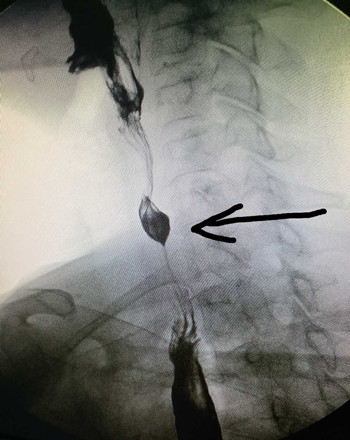

時隔1月,我科又于2017-03-06 17:00接診了第二例食管異物患者。該患者于6小時前進食時誤咽棗核,當(dāng)時感咽部疼痛,無咳血及呼吸困難,無嗆咳,進食時疼痛加重。門診檢查食道造影示:第7頸椎平面可見異物。門診醫(yī)師遂以“食道異物”收住入院。入院后張立剛副主任醫(yī)師及劉教練主治醫(yī)師立即安排各項術(shù)前工作,急查上消化道鋇餐造影示:胸1椎體重疊處見梭形高密度影,結(jié)合食管造影,確定為食道異物。為防止患者出現(xiàn)食道感染及穿孔,遂急診在全身麻醉下行食道異物取出術(shù)。用硬質(zhì)食道鏡直視下見食管入口下約2cm有一棗核,垂直扎入食管壁,有少許滲血,故異物鉗夾住棗核后慢慢退出,檢查食管壁無活動性出血后結(jié)束手術(shù)。從患者入院到手術(shù)結(jié)束,整個過程不到3小時。